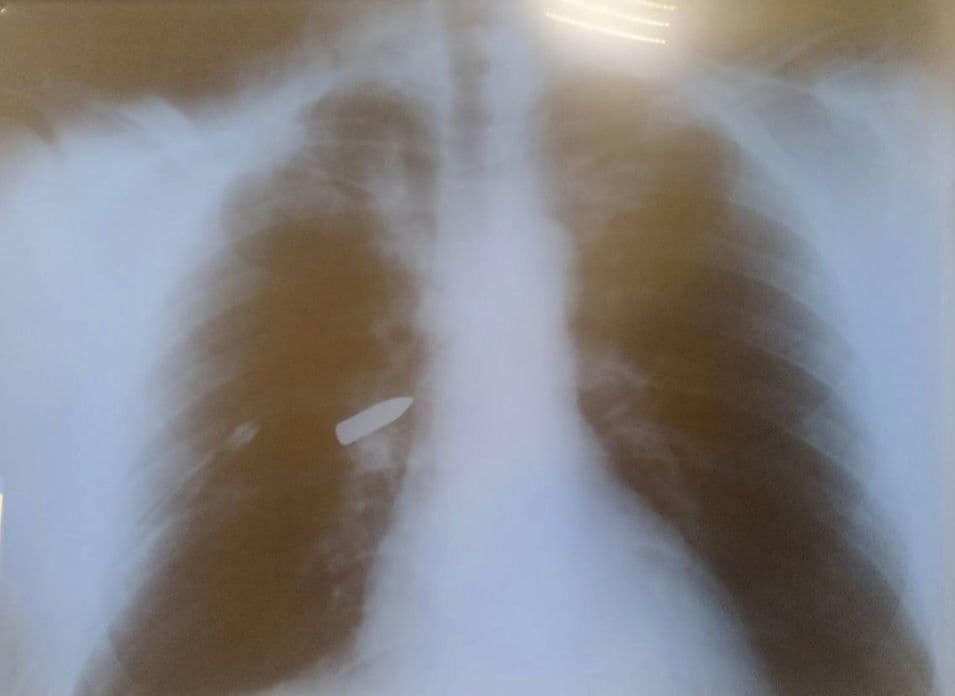

В Днепре врачи спасли тяжело раненого военного с вражеской пулей в легких.

Как сообщили в Департаменте здравоохранения населения, 40-летний военный получил тяжелое ранение во время боев. Вражеская пуля застряла внутри легкого. Военные хирурги оказали мужчине первую медицинскую помощь и эвакуировали его в Днепр.

Хирурги торакального отделения больницы №16 провели военному рискованную операцию. Они уверяют, что шансов на спасение было мало.

Тяжелая операция длилась несколько часов. Медикам удалось спасти еще одну жизнь благодаря командной работе и сильному духу защитника.